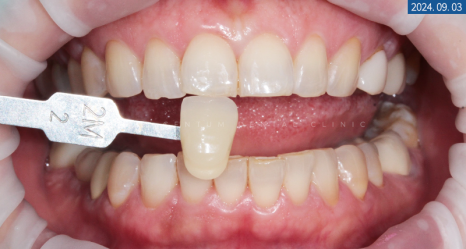

가장 먼저 원하시는 디자인과 색상을 확인하기 위해

쉐이드 체크와 가이드 형태를 보여드렸습니다.

보시고 나서 단정하고 깔끔한 걸로 요청 주셨기에

톤을 1.5단계를 높인 것으로 결정하게 됐습니다.